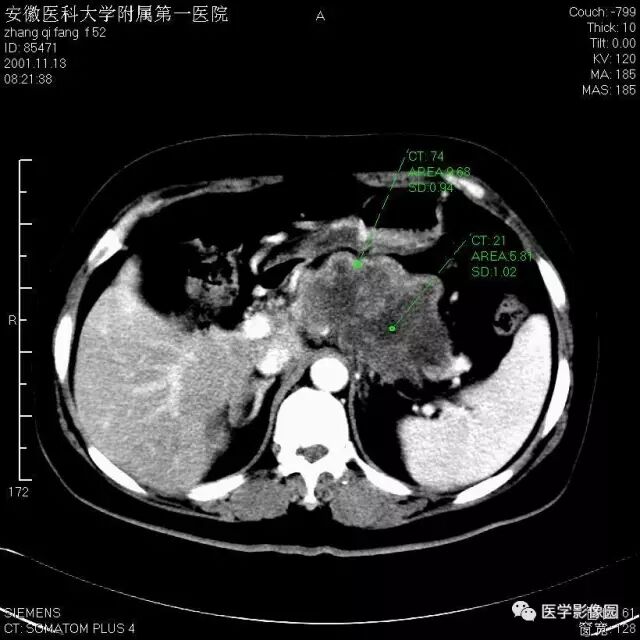

图6-4-9胰腺癌

A.CT平扫见胰头等密度肿块,

钩突明显圆隆;

B.增强扫描动脉期钩突内见境界

不清低密度灶(↑);

C.胰头部可见扩张的胆总管(↑)和

主胰管(长↑),即双管征